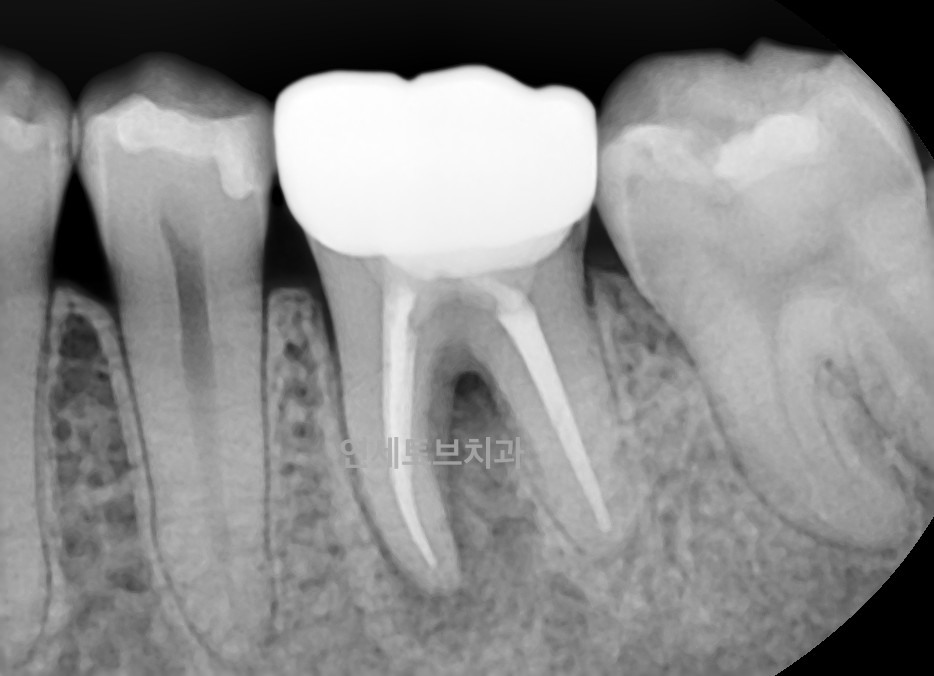

Case #2

치료 전

재근관치료